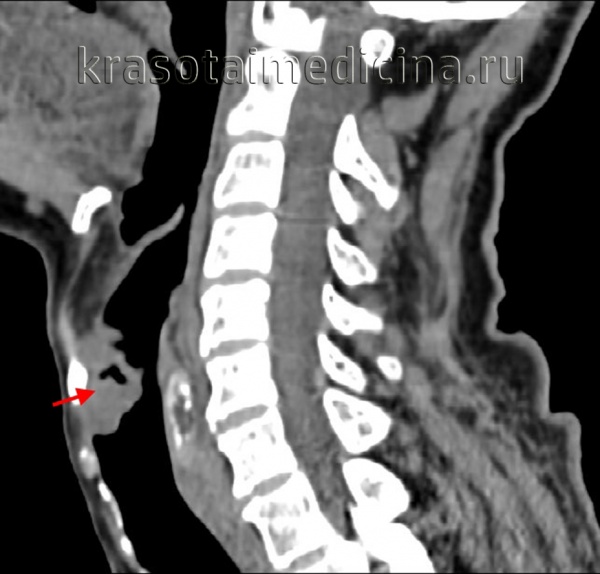

(Справа) При аксиальной КТ с КУ определяются аналогичные изменения: инвазия окологортанной жировой ткани с обеих сторон и левой черпалонадгортанной складки. Опухоль выбухает через вырезку щитовидного хряща. Грушевидный синус не изменен. (Слева) При аксиальной КТ с КУ визуализируется небольшое объемное образование в надгортаннике с признаками инвазии предгортанного пространства (стадия Т3). Опухоль симметрична, что затрудняет ее выявление, тем не менее, надгортанник никогда не должен выглядеть настолько утолщенным или накапливать контраст, как здесь. Лимфоузлы этом случае не определяются (их следует искать с обеих сторон, особенно при опухолях надгортанника.